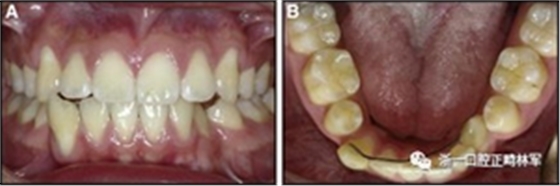

臨床檢查顯示固定保持器完好,弓絲沒(méi)有斷裂(圖13)。在下頜右側(cè)中切牙唇側(cè)和鄰近側(cè)切牙的舌側(cè)注意到有牙齦退縮。這些牙齒在退縮方向上存在顯著的扭矩差異。下頜的左側(cè)尖牙頰側(cè)錯(cuò)位,而右側(cè)尖牙舌側(cè)傾斜。三維射線照片證實(shí)了下頜右側(cè)尖牙面?zhèn)妊啦酃菃适?,右?cè)中切牙的喪失程度較輕。右側(cè)側(cè)切牙根也從舌側(cè)骨面上扭轉(zhuǎn)出來(lái)(圖14)。

圖13.粘合到尖牙和切牙上的柔性螺旋弓絲保持器,伴有牙齦退縮和附著喪失,中切牙之間嚴(yán)重的扭矩差異以及兩顆尖牙的橫向移動(dòng)和扭矩。牙周問(wèn)題和牙齒移動(dòng)的嚴(yán)重程度均為牙周正畸聯(lián)合治療的指征:A,正面視圖; B,咬合面視圖。